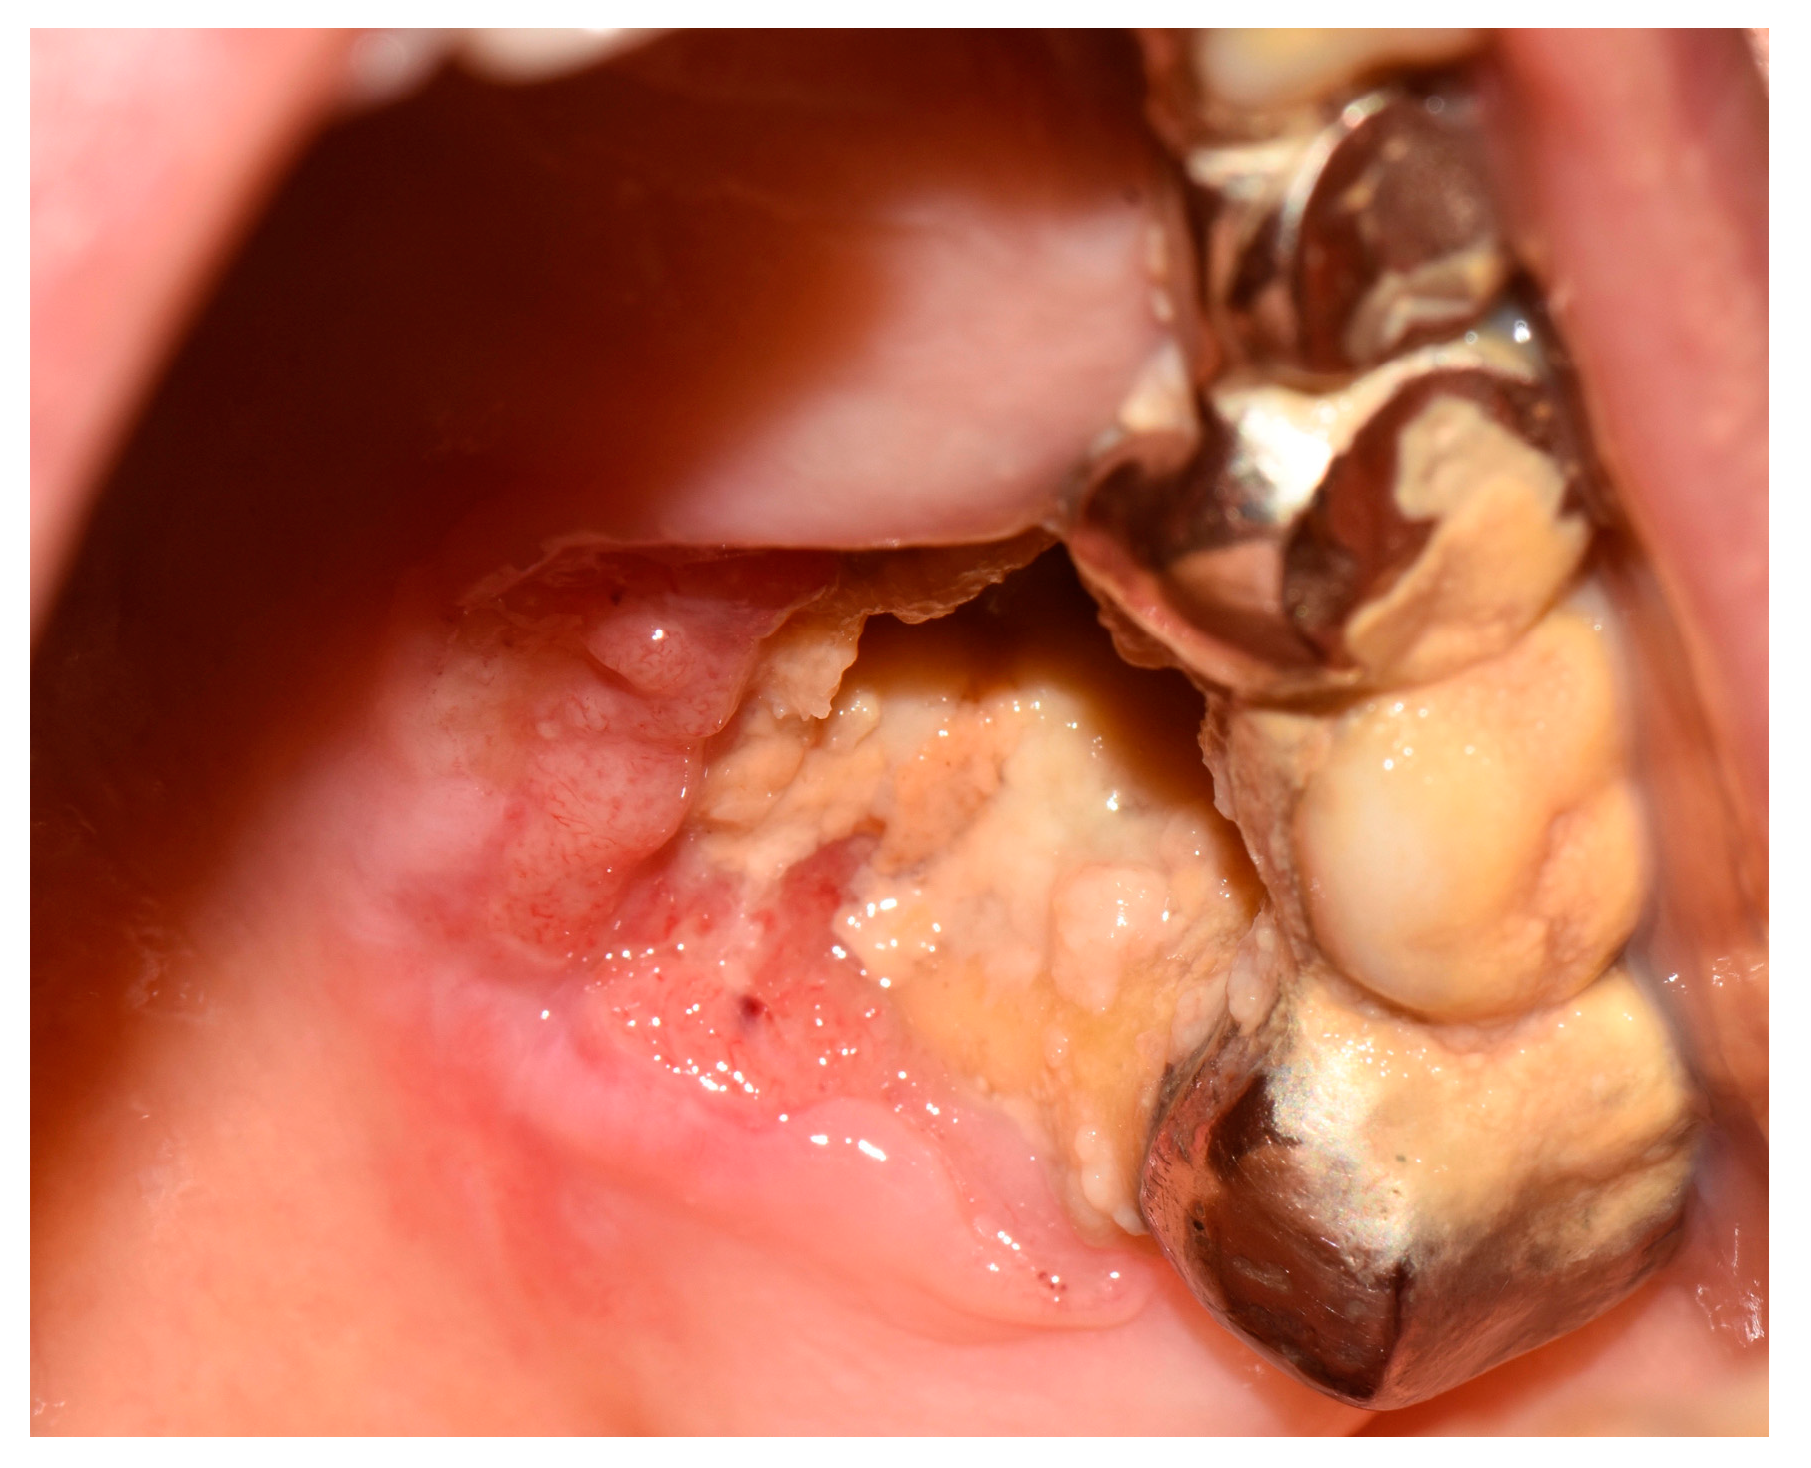

A Case of Difficult Diagnosis: A Squamous Cell Carcinoma with Bone Exposure and Oro-sinus Communication in a Patient Receiving Alendronate †